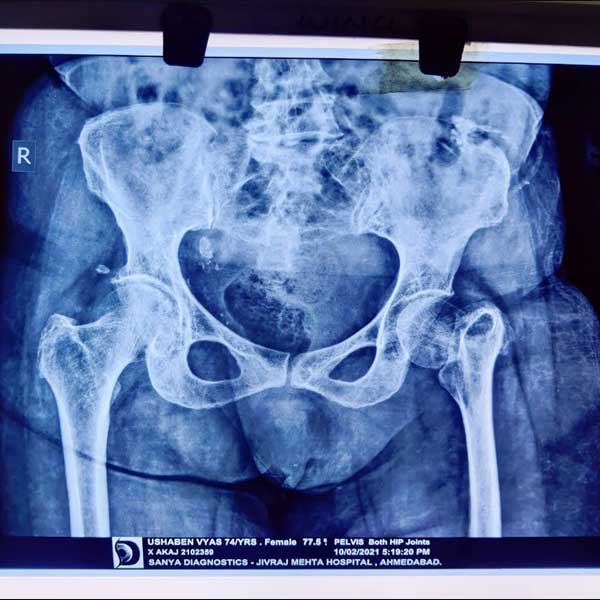

Case 1 - Hip Hemiarthroplasty

A female patient, aged 72 years. She had been diagnosed to have a Closed fracture of neck Fracture. She was treated operatively with Hip Hemiarthroplasty.

Pre-Operative